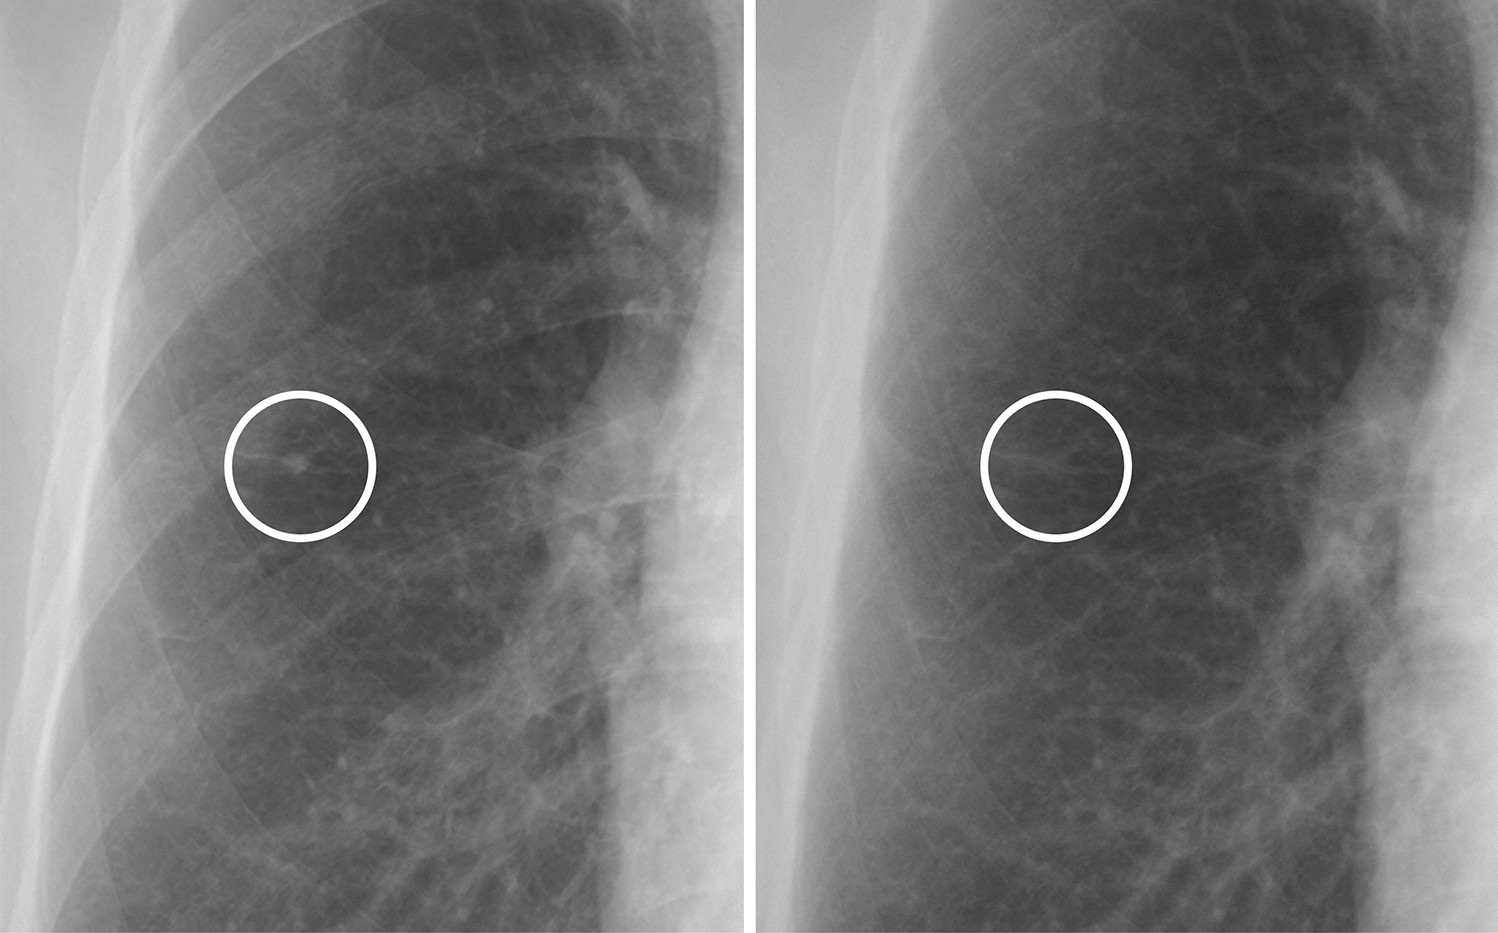

Figure 2

A case of a calcified nodule not overlapping with the bone. (left) On the standard image, the evaluation of the presence or absence of calcification among readers was not consistent (confidence level of each reader: 1, 3, 2, 3 and 2, respectively). (right) In the soft tissue image, the nodule disappeared. All readers correctly evaluated it as calcified (confidence level of each reader: 1, 1, 2, 1 and 2, respectively).